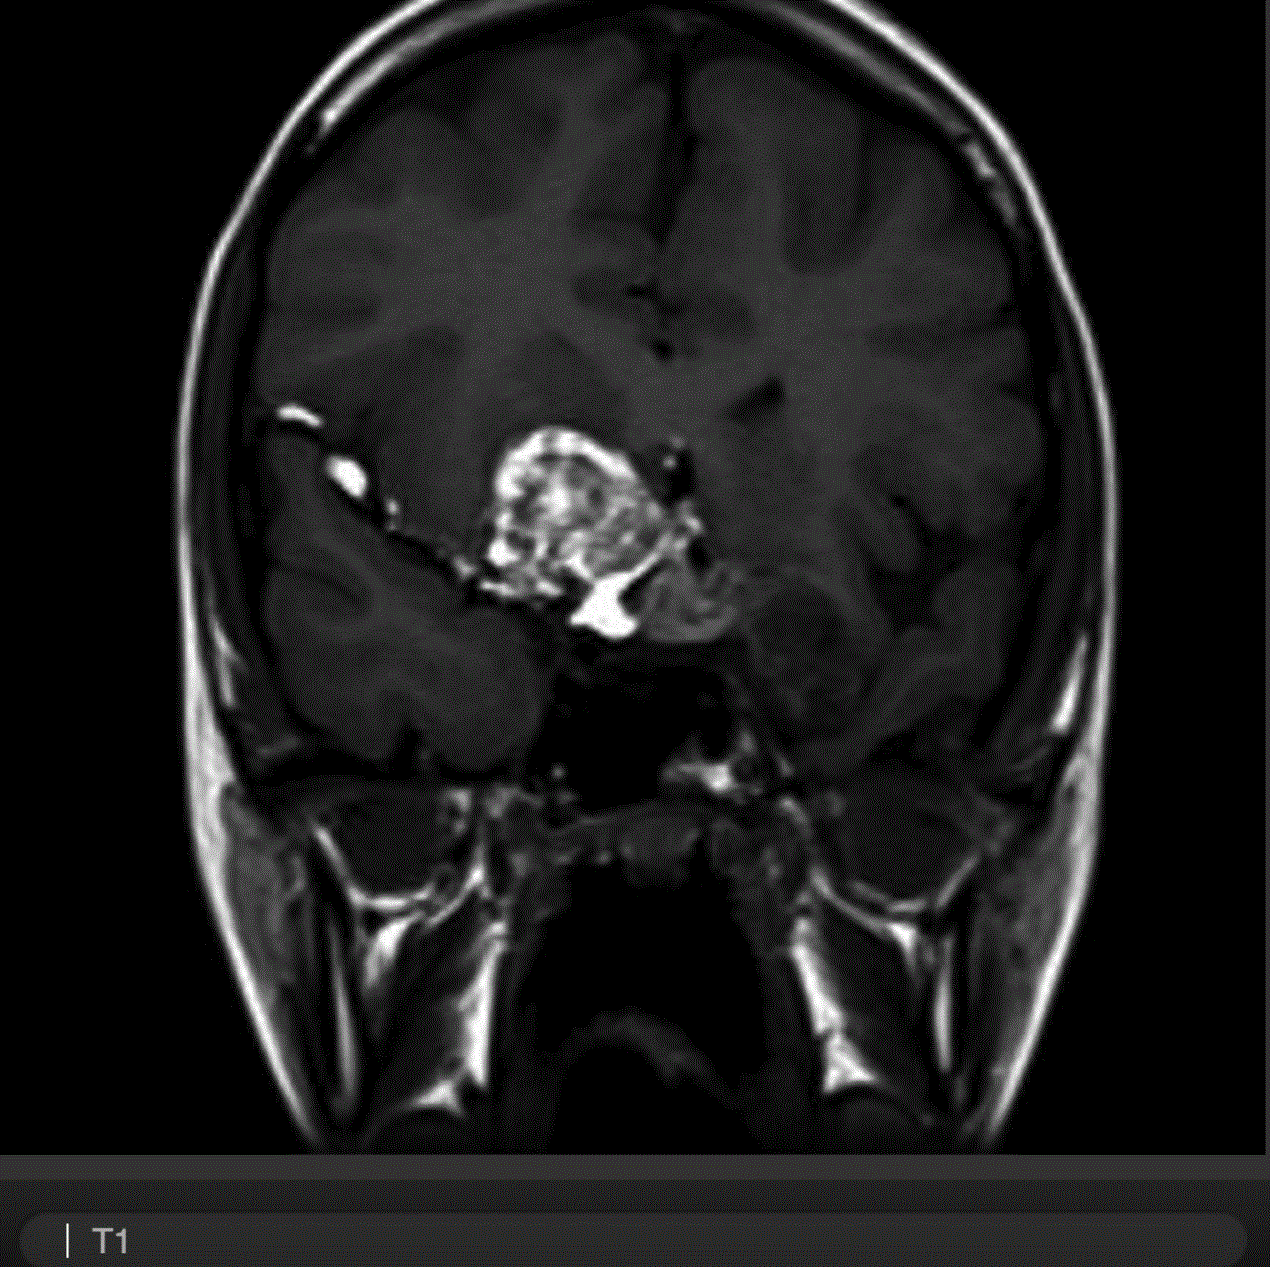

B. 冠状位T1WI

可见鞍区占位,向上压迫视交叉,向两侧压迫海绵窦和颈内动脉,占位右下部分在T1W1上有一圆形高信号,提示瘤内出血。